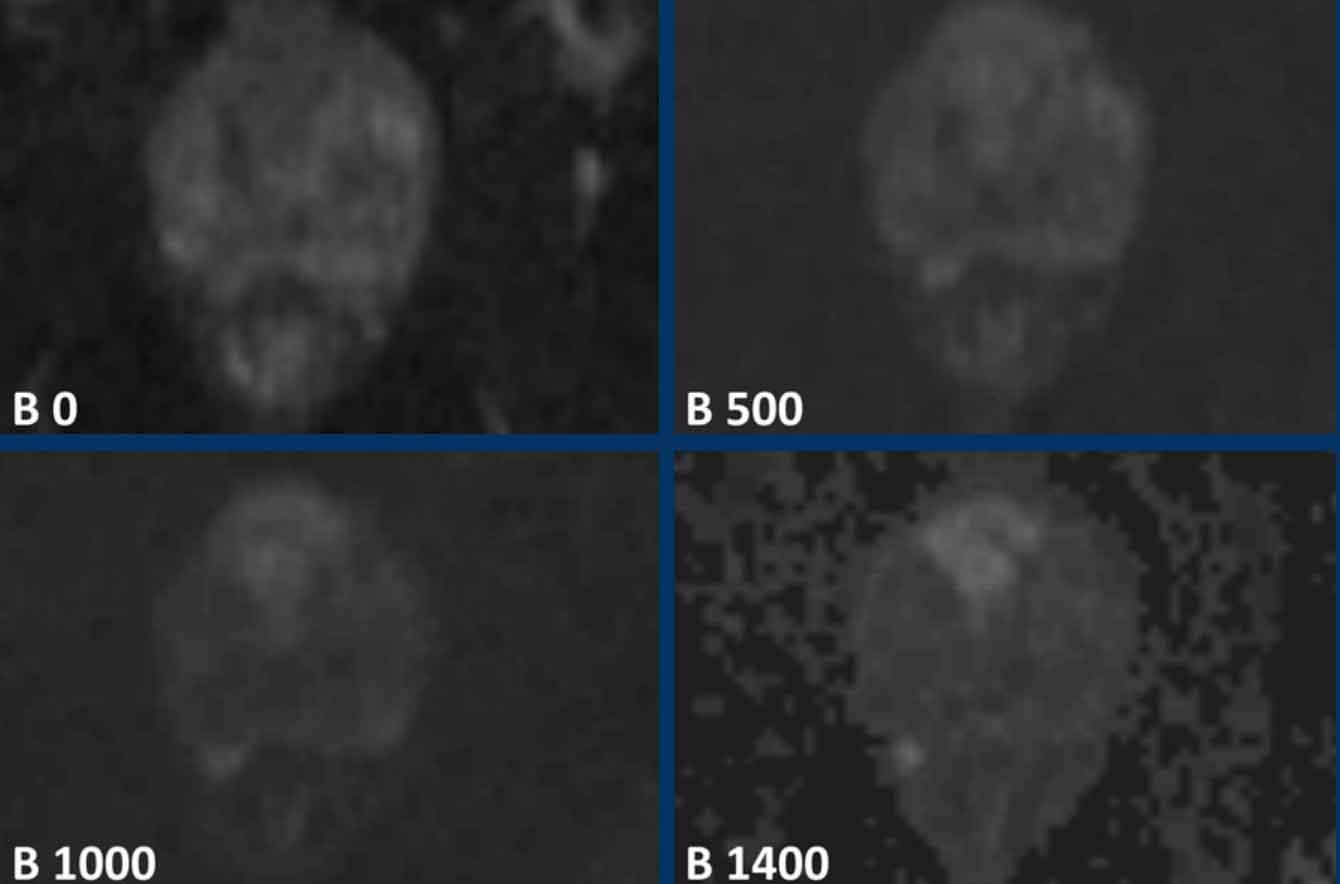

DWI

Hạn chế khuếch tán được xác định khi một tổn thương có tăng tín hiệu trên DWI tương ứng với giảm tín hiệu trên bản đồ ADC, điều này có tương quan cao với sự hiện diện của tế bào ác tính.

Giá trị ADC chính xác của tổn thương có tương quan nghịch với khả năng tổn thương đó là ác tính.

Giá trị b cao là cần thiết để tạo tỷ lệ tín hiệu trên nhiễu cao.

Khuyến nghị giá trị b tối thiểu là 1400.

Lưu ý sự khác biệt giữa ảnh B1000 và B1400.

Sinh thiết có hướng dẫn hợp nhất (fusion) của tổn thương ở phía trước tuyến tiền liệt cho thấy Gleason 3+4.